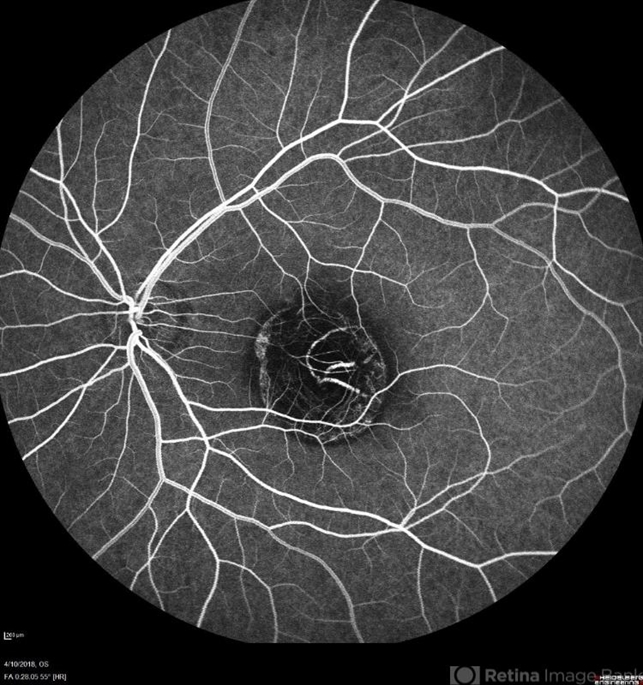

- macular dystrophy, central areolar choroidal dystrophy (CACD), retinal dystrophy, hereditary retinal dystrophy

- Hamza Shawky, Alferdaws eye hospital, Retina unit

- Heidelberg Spectralis

- Left fundus late FFA photograph of a 35-year-old man with central areolar choroidal dystrophy, BCVA is 6/60